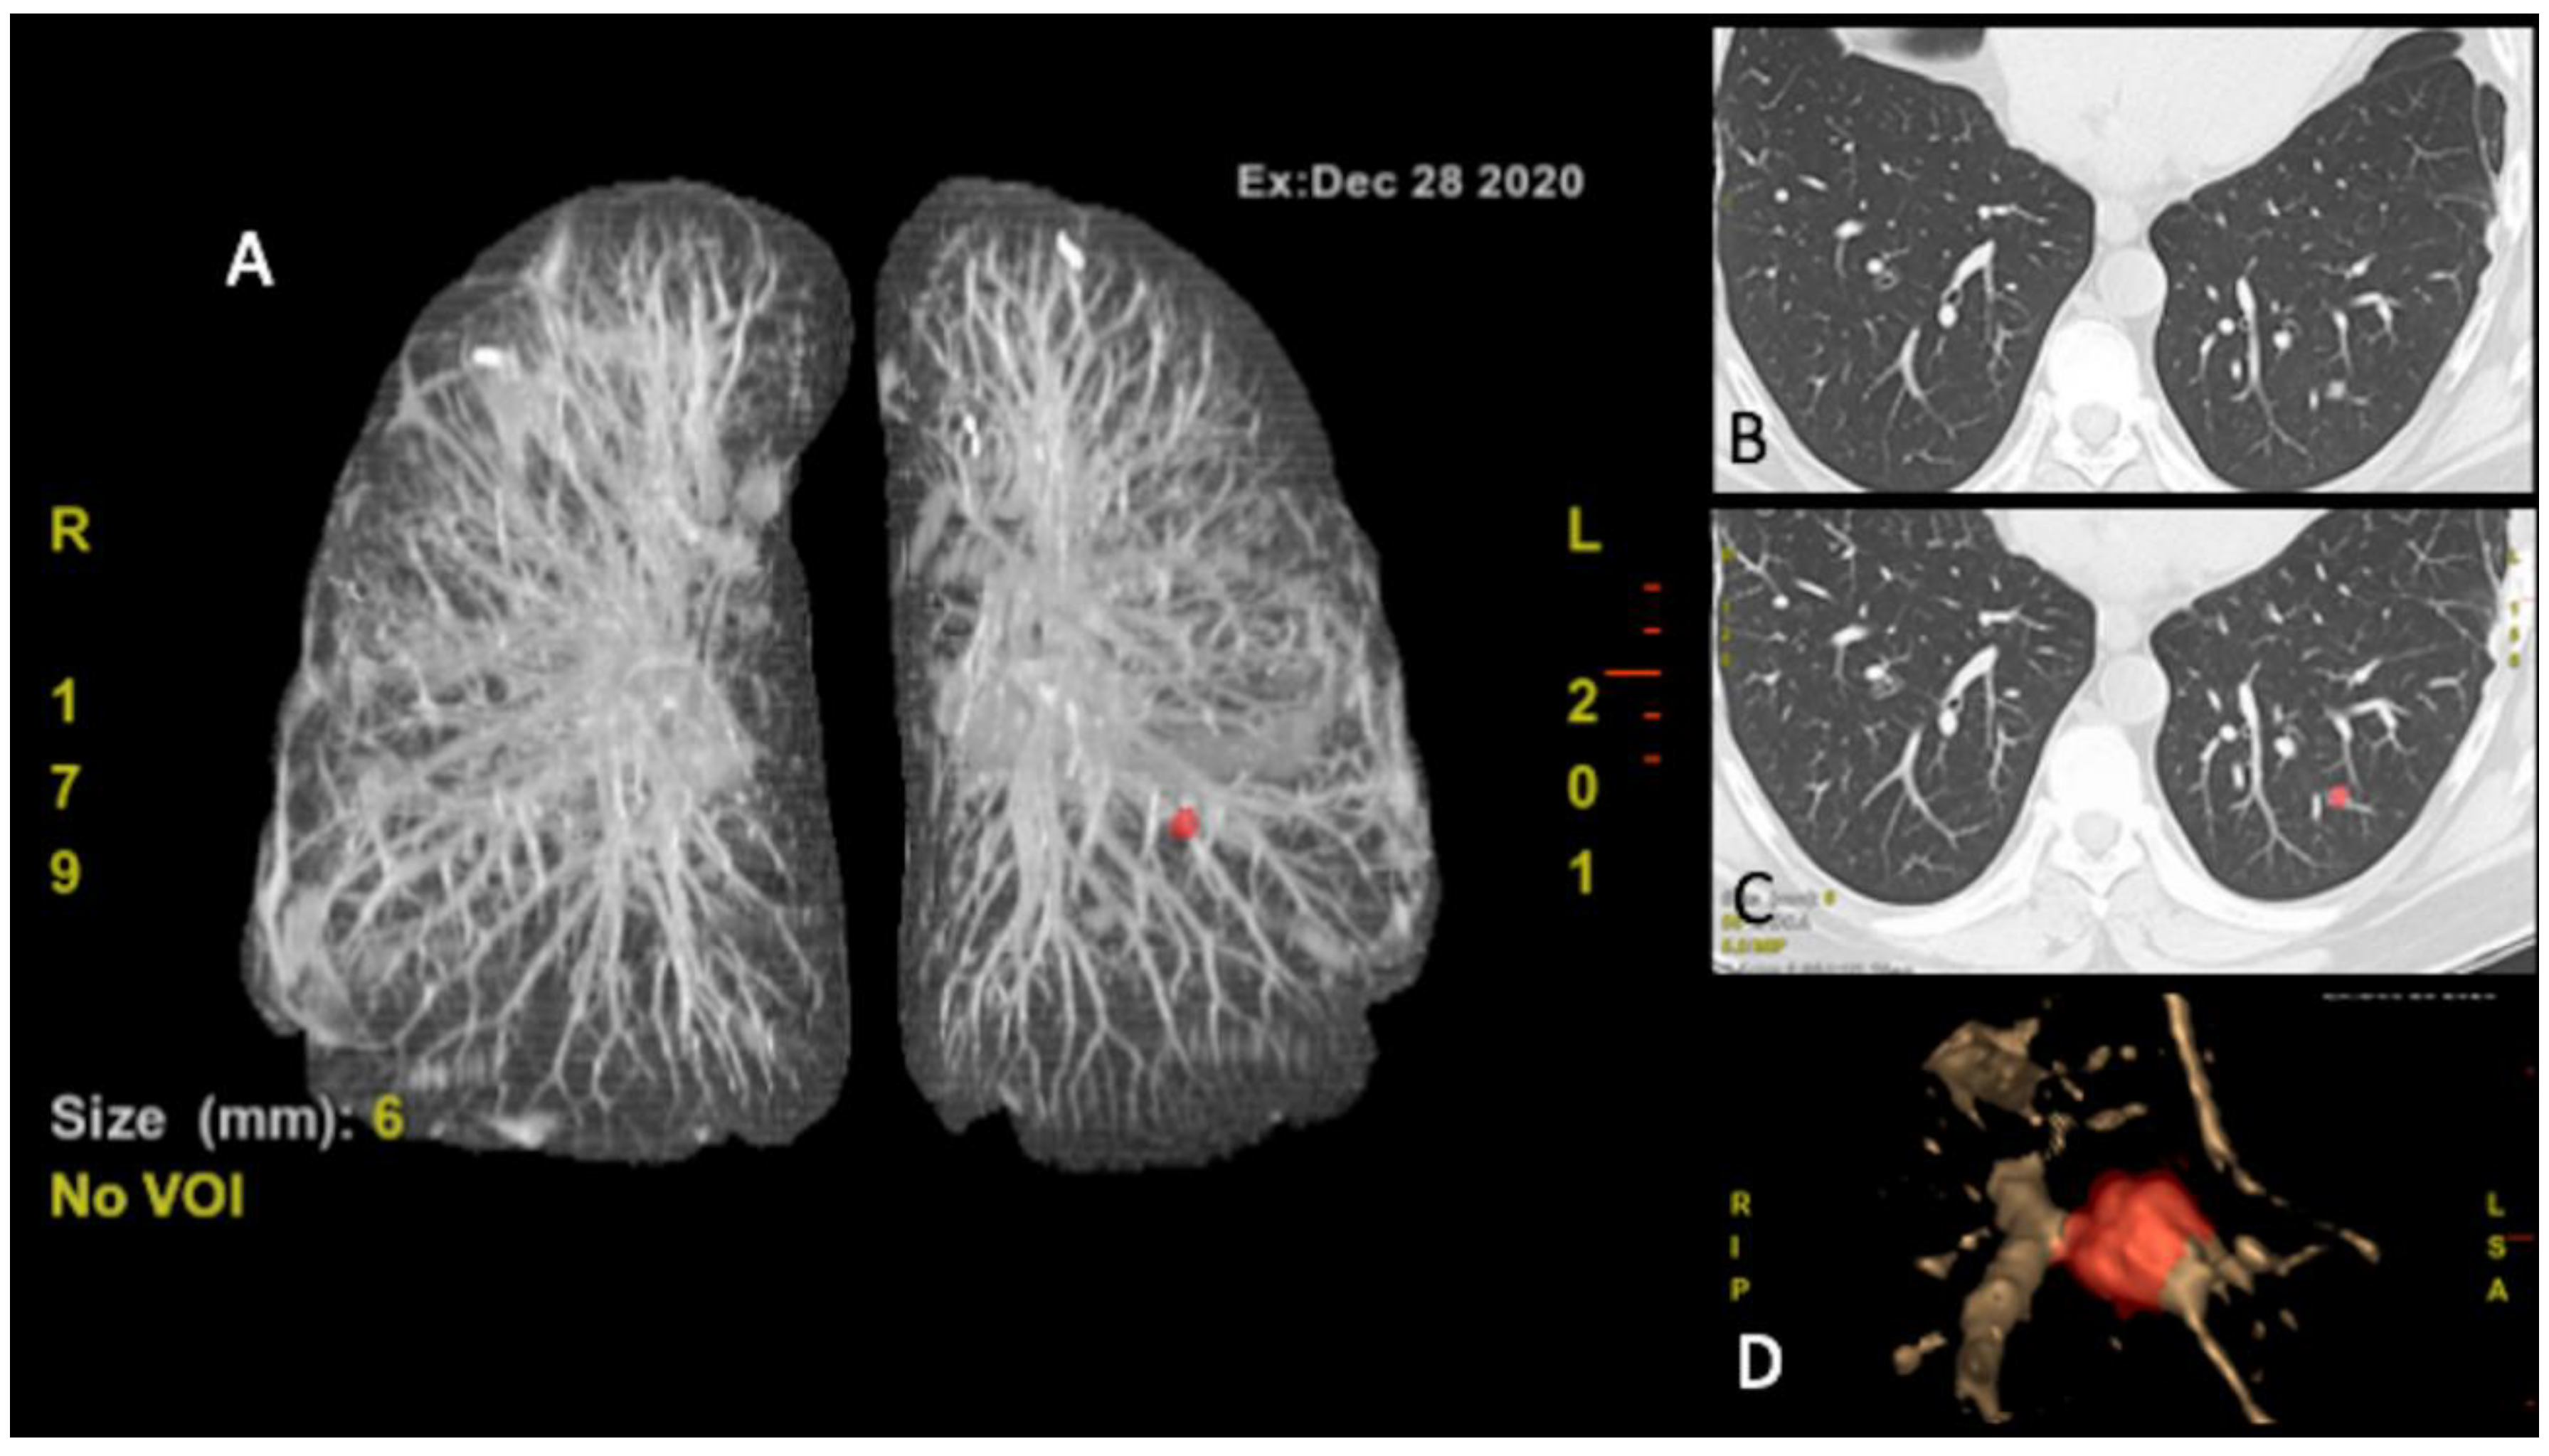

3.3.3. Computer-Aided Diagnosis (CAD)

- Shariaty, F.; Mousavi, M. Application of CAD systems for the automatic detection of lung nodules. Inform. Med. Unlocked 2019, 15, 100173. [Google Scholar] [CrossRef]

- Jacobs, C.; van Rikxoort, E.M.; Twellmann, T.; Scholten, E.T.; de Jong, P.A.; Kuhnigk, J.M.; Oudkerk, M.; de Koning, H.J.; Prokop, M.; Schaefer-Prokop, C.; et al. Automatic detection of subsolid pulmonary nodules in thoracic computed tomography images. Med. Image Anal. 2014, 18, 374–384. [Google Scholar] [CrossRef]

- Drew, T.; Vo, M.L.-H.; Olwal, A.; Jacobson, F.; Seltzer, S.E.; Wolfe, J.M. Scanners and drillers: Characterizing expert visual search through volumetric images. J. Vis. 2013, 13, 1–13. [Google Scholar] [CrossRef]